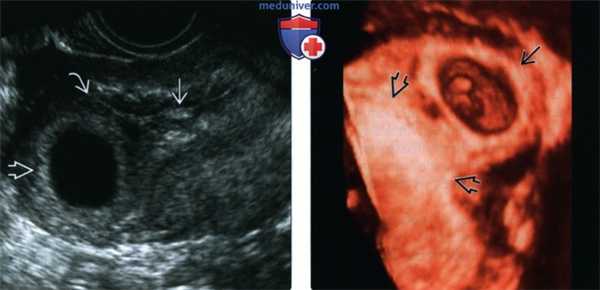

(Слева) При ТВУЗИ видна внутриматочная структура, напоминающая плодное яйцо, с одним заостренным краем. Она расположена центрально в полости матки, но имеет вид, характерный для признака двойного децидуального кольца. Сочетание признаков наблюдается довольно часто.

(Справа) При ТВУЗИ у этой же пациентки визуализируются кровоизлияние в желтом теле в левом яичнике и прилежащие петли кишечника. ВМБ бывает очень трудно диагностировать, и у данной пациентки в отсутствие более тщательного обследования могла бы быть констатирована возможная МБ. (Слева) При ТВУЗИ у этой же пациентки видно гетерогенное объемное образование в области левого придатка, которое отделено от яичника. Таким образом, теперь картина больше соответствует возможной ВМБ. Повторные исследования выявили увеличение размеров объемного образования и изменение формы скопления жидкости в полости матки. При лапароскопии была подтверждена левосторонняя трубная беременность.

(Справа) В макропрепарате маточной трубы после сальпингэктомии у пациентки с трубной беременностью с разрывом трубы виден эмбрион.